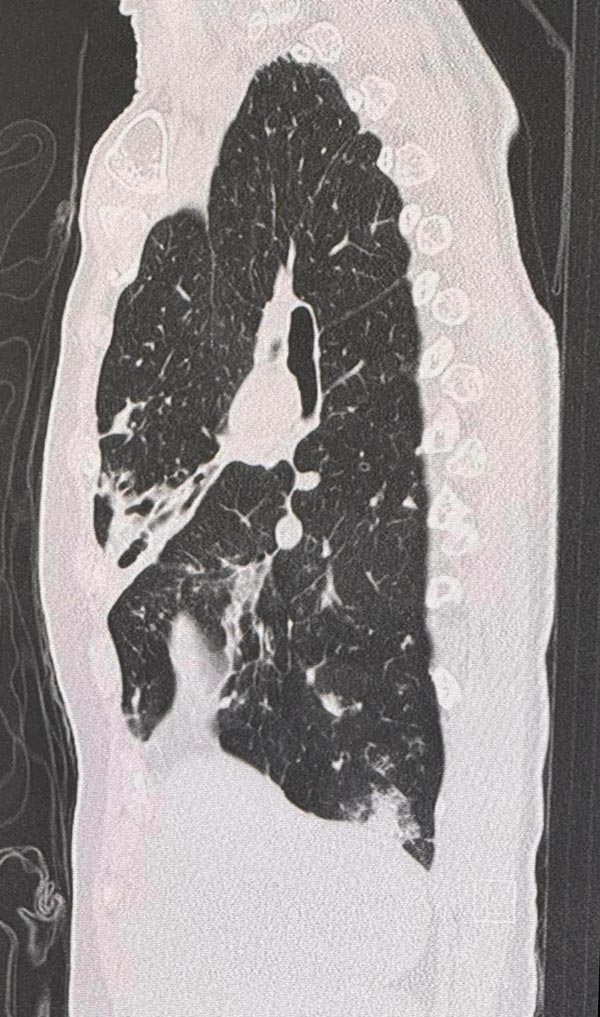

ตรวจร่างกาย ฟังปอดมีเสียงผิดปกติทั้ง 2 ข้าง เอกซเรย์ปอดผิดปกติเข้าได้กับหลอดลมโป่งพองทั้ง 2 ข้าง ทำคอมพิวเตอร์ปอดเห็นหลอดลมโป่งพองในปอดทั้ง 2 ข้าง ส่งเสมหะย้อมเชื้อหาวัณโรค AFB smear ให้ผลบวก

วินิจฉัย : โรคหลอดลมโป่งพอง สงสัยติดเชื้อวัณโรค หรือวัณโรคเทียม จึงให้ยา INH, rifampicin, ethambutol รักษาวัณโรค ร่วมกับ azithromycin รักษาวัณโรคเทียม 2 สัปดาห์ หลังกินยาดีขึ้น หยุดไอ ไม่มีเสมหะ